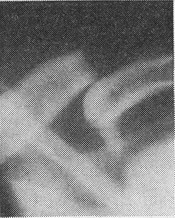

![]() Рис. 5. Закритий поперечний перелом ключиці зі зміщенням |

Симптоми. В області перелому видно припухлість і нерідко крововилив; при пальпації відзначається локальна болючість, часто вдається промацати кінець центрального уламка, що виступає під шкірою (рис. 5). Рухи в плечовому суглобі болючі і обмежені. Як правило, визначається кісткова крепітація.